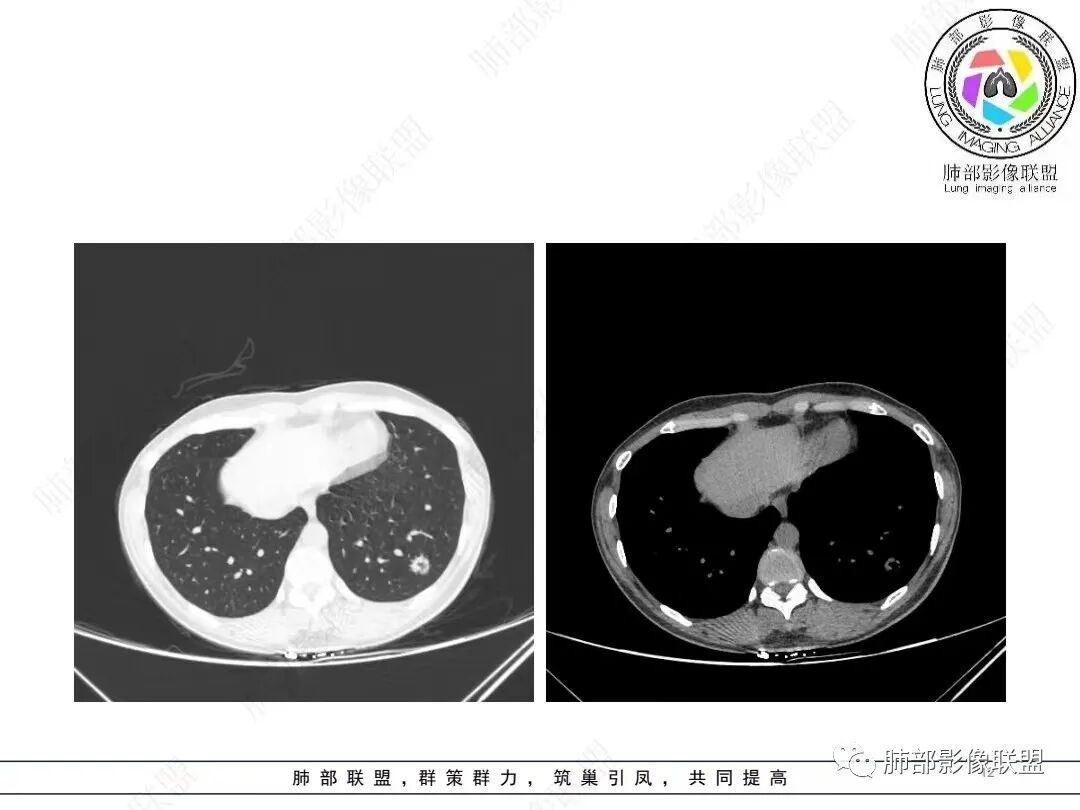

1、临床特点: 37岁女性,体检发现肺结节,2年前有甲状腺腺瘤手术史。实验室无阳性发现。

2、影像特点:左肺下叶类圆形结节影,周围可见多发细小毛刺,浅分叶,张力不高,未见胸膜牵拉。病灶内隐约见空泡影(未提供CT值),近端部分血管呈杵状增粗,可疑脐凹征。增强后实性部分有轻度强化。外围病灶,与支气管关系不明确。